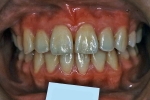

| 治療後3年経過時